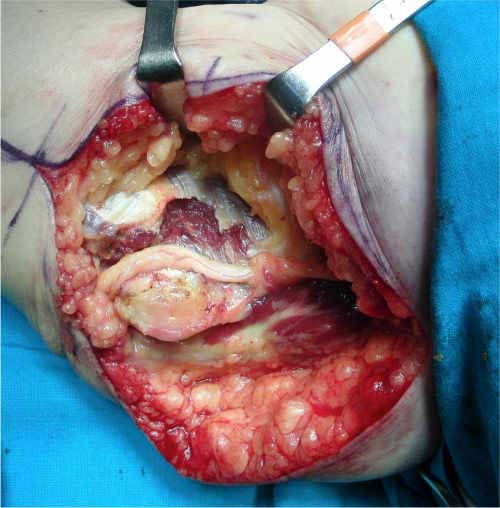

En estos casos optamos por realizar una mínima resección de la epitróclea y recubrimiento con fascia (epitroclectomía más epitrocleoplastia) (figuras 6 y 7), porque no devasculariza al nervio tanto como las transposiciones nerviosas, dejando éstas para las recidivas o deportistas profesionales de lanzamiento (béisbol, jabalina…) (figura 8).

Fig. 6: mínima resección de la epitróclea

Fig. 7: epitrocleoplastia con fascia

Fig. 8: liberación submuscular